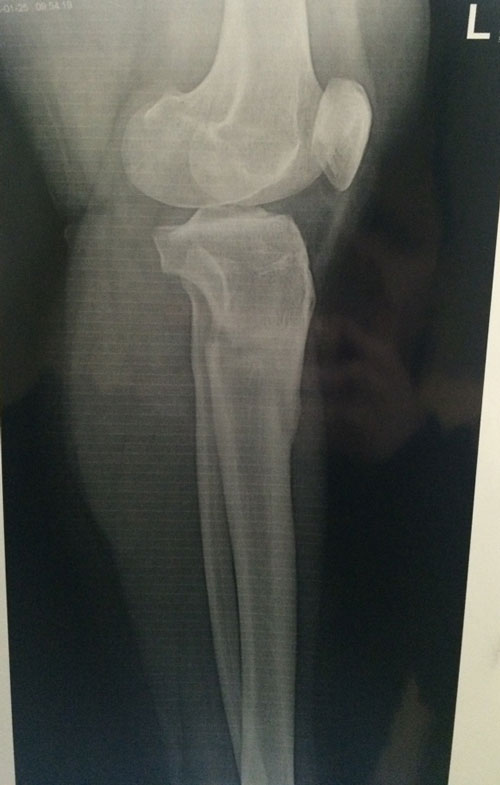

Ножки супер! разрешено всё без ограничений, все нагрузки: спорт, фитнес, каблуки любых размеров - Вам очень они пойдут! Нельзя: беременеть в течении первых 6 месяцев с момента снятия аппаратов!